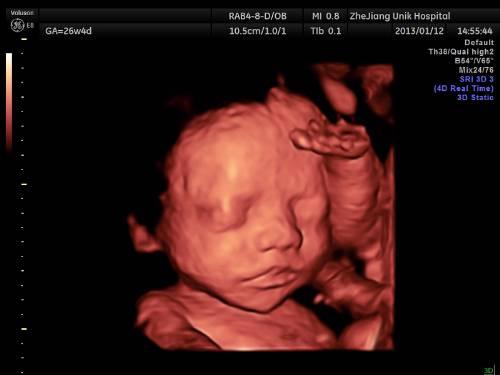

四维彩超也是通过B超看胎宝宝发育是否正常。它是在三维彩超成像的基础之上,增强了三维立体图像的实时性与真实性,给三维立体图像赋予了动态的感受,使诊断变得更加清晰和全面,可以看到胎宝宝在妈妈肚子里一连串的动作,比如,通过四维彩超观察到胎儿的微笑、眨眼等动作,是动态的影像。

由于四维彩超能够表面成像,所以照出来会更清晰,现在很多的医院也有人文的考虑,会在检查过程中,把胎宝宝的活动状态刻成光盘,宝宝的相貌打印成照片,送给新爸爸妈妈们。除了能排除胎宝宝畸形,同时也可以让爸爸妈妈留个纪念